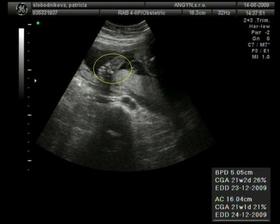

Vzali sme sa 26.7.2008, teraz plánujeme bábatko...hak som prestala brat vo februari..prvy cyklus sa nezadarilo...druhy je ten stastny, nasli sme si //...este nam to treba potvrdit od dr...20.4. vysetrenie u dr - na ultrazvuku je vidiet dutinku, ktorá má 3,7mm 🙂)) 27.4.dutinka ma 11mm a nasa bublinka má 3,6mm 🙂) 22.5. - prvá poradňa, všetko je ok 🙂 9.6.- NT utz, vsetko ok 🙂)

Termín pôrodu vychádza na 24.12.2009 - takže bude vianočný darček 🙂)) 6.7.odber krvi na AFP testy, 15.7.su vysledky a vsetko je ok 🙂) 14.8. 4D ultrazvuk - máme 413g (22tt) a vyzerá to na dievčatko 🙂)) TP podla velkosti: 23.12. 13.10. - utz v 30tt, resp.takmer v 31tt..máme 1700g..podľa veľkosti 31+2tt a všetko ok 🙂)